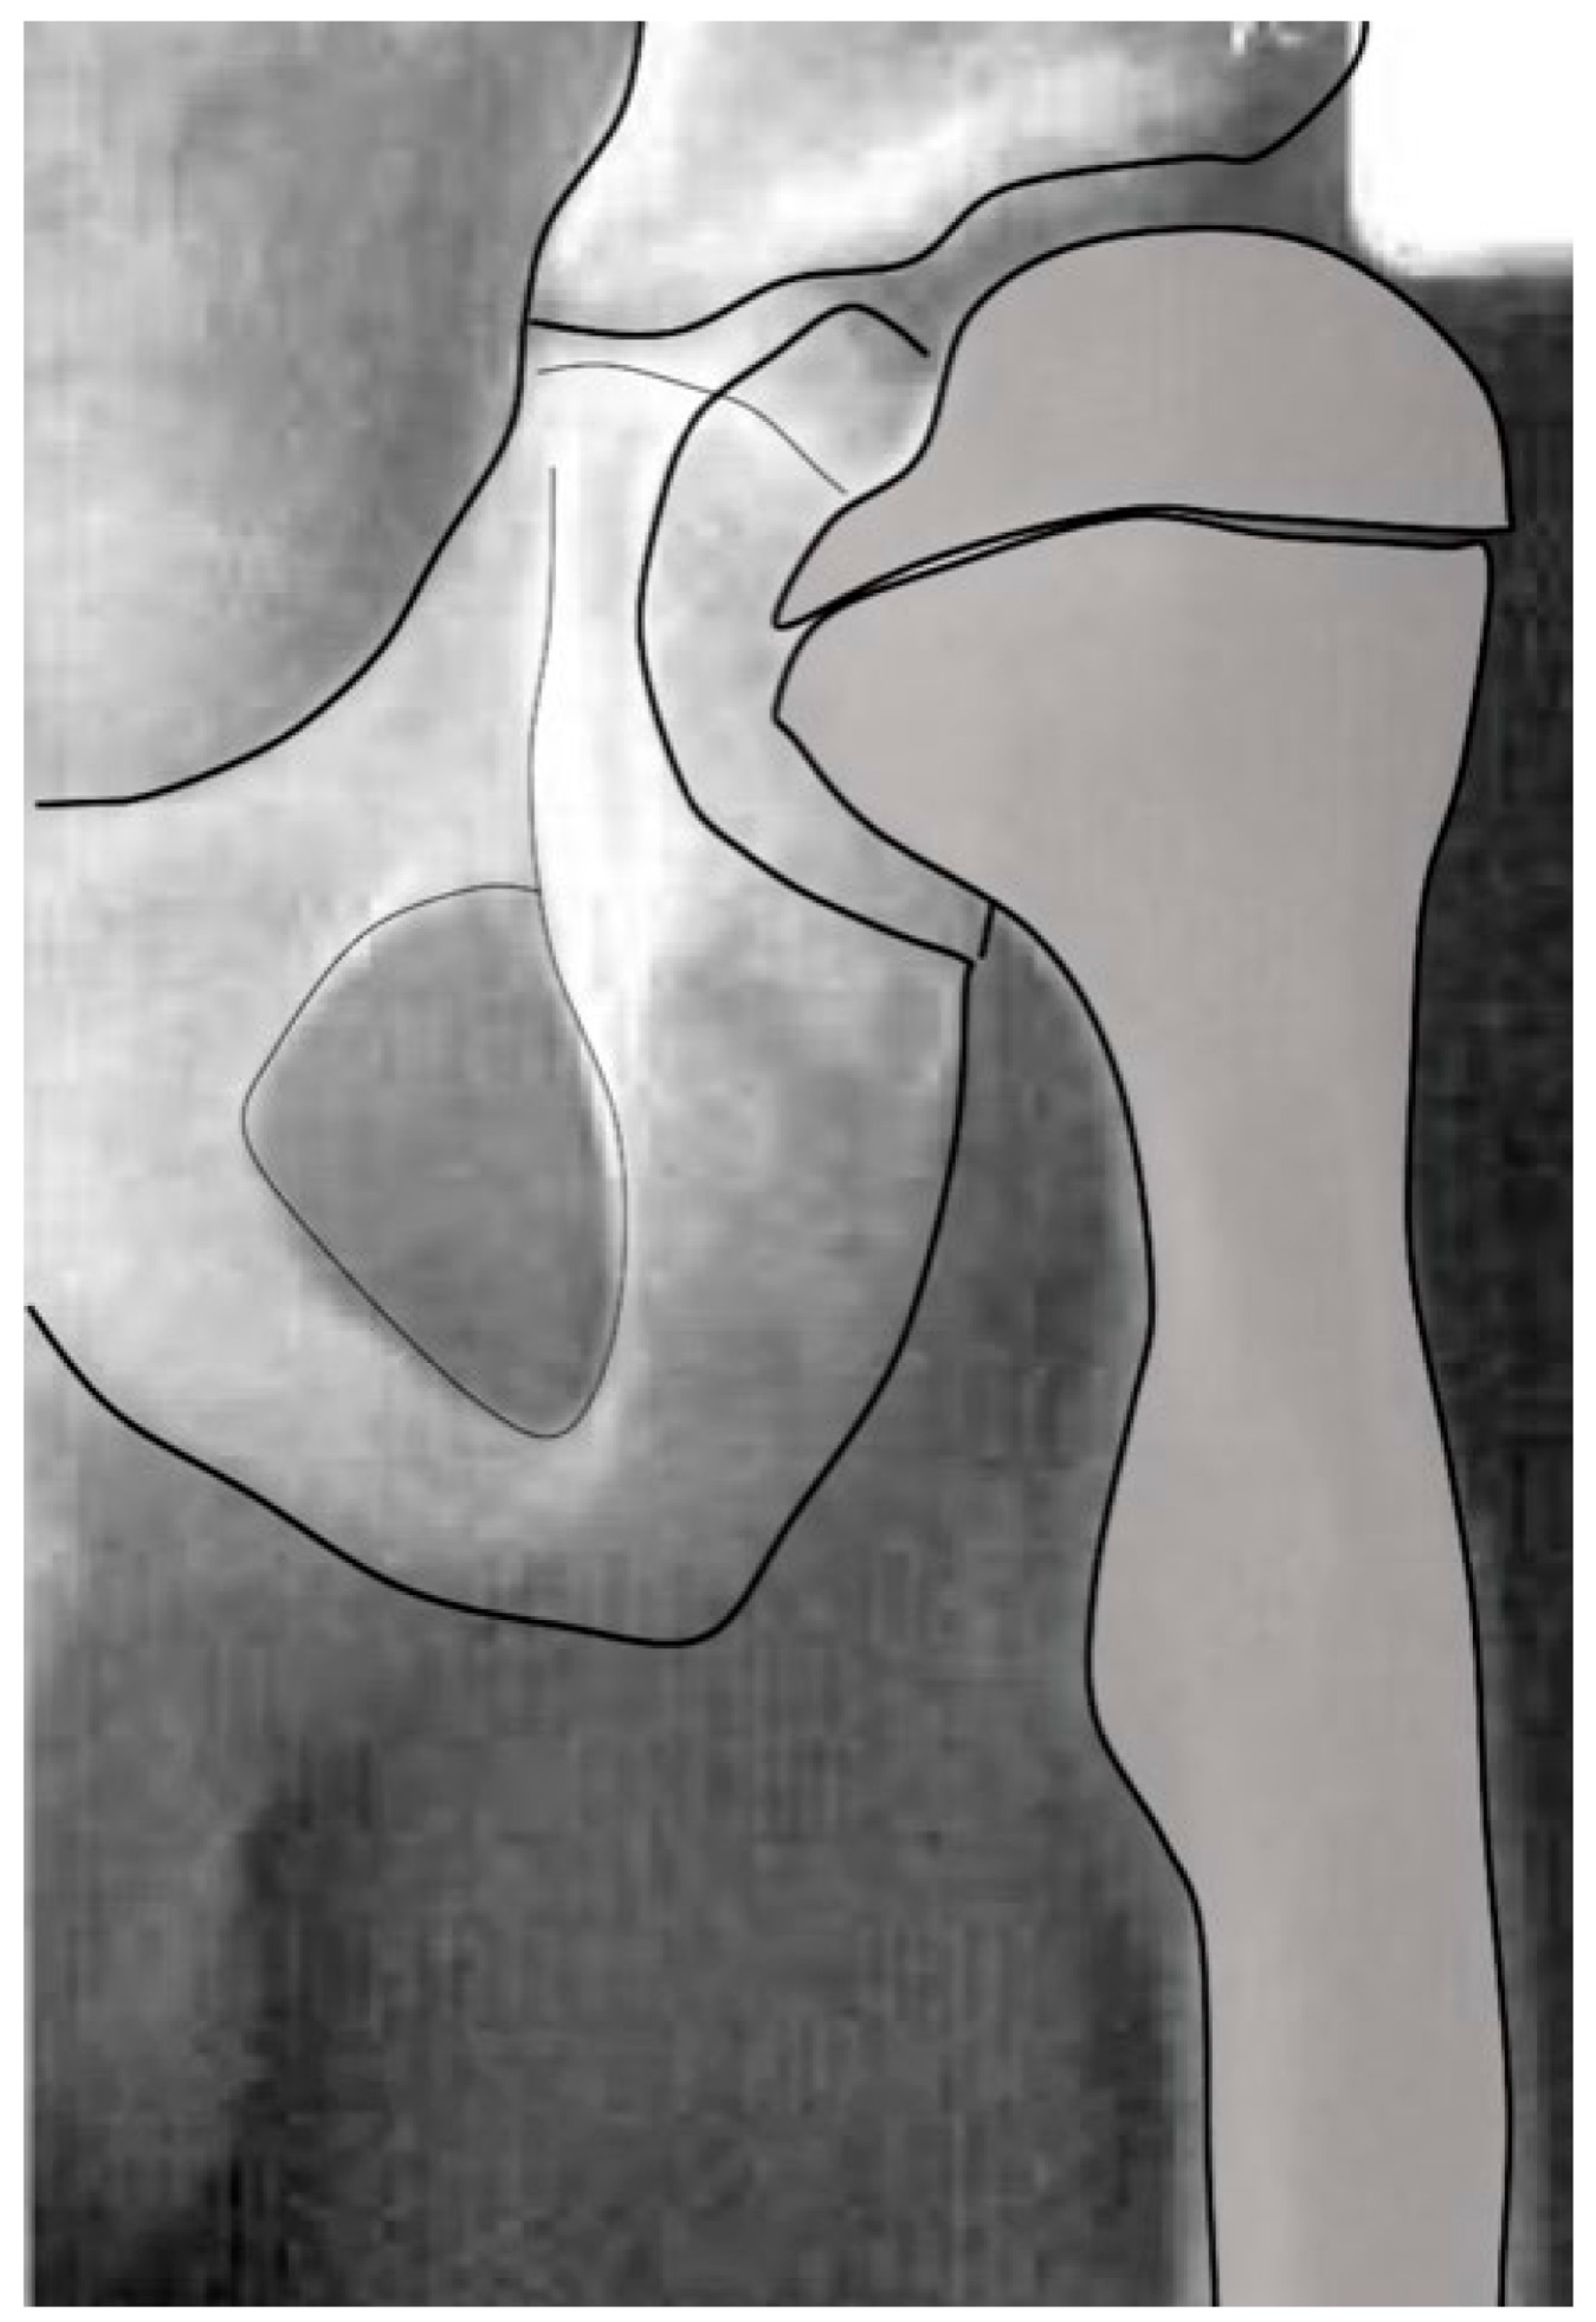

3.4. Femoral Factors Influencing Hip Pathology

3.4.1. Pathologic Role of Femoral Anteversion

3.4.2. Pathologic Role of Coxa Valga and the Impact of its Correction on Spastic Hips

4.1.2. Pathologic Role of Coxa Valga and the Impact of its Correction in Weak and Hypotonic Hips

4.1.3. Pathologic Role of Coxa Valga and Treatment Options in Paralytic Hips